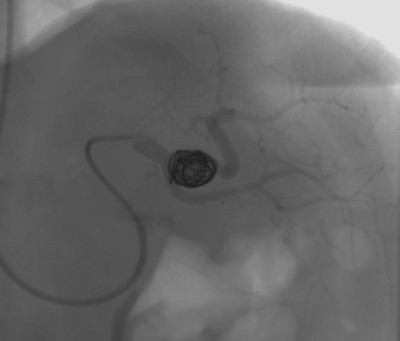

При большой или быстро растущей аневризме, при угрозе разрыва выбирается оперативное вмешательство. Предпочтение отдаётся малоинвазивным методам: эндоваскулярной (внутрисосудистой) хирургии: стентированию и эмболизации САС — закрытие полости выпячивания с помощью специальных материалов или препаратов. Вмешательства проводятся под рентген-контролем.

Высокий уровень хирургической помощи обеспечен многолетним опытом оперирующих врачей. В клинике проводятся все виды операций, включая малоинвазивные рентгеноэндоваскулярные (эндопротезирование, эмболизация